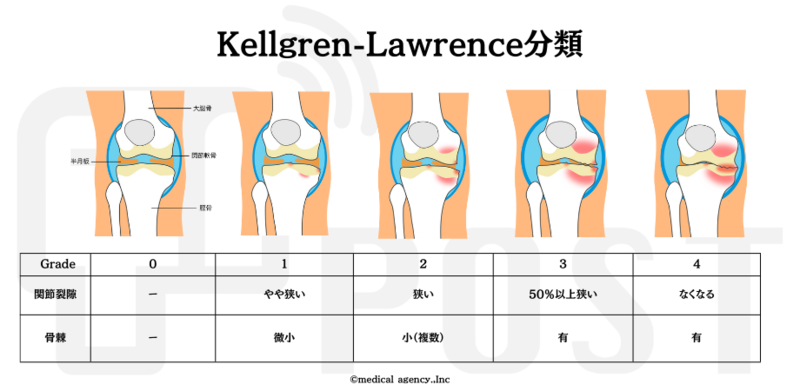

医師が変形性膝関節症と診断した場合、医師は次の基準に基づいて重症度グレード 0 ~ 4 に基づいて画像にラベルを付けます。

レントゲンで見た変形性膝関節症の4つの特徴は何ですか?

X 線写真で確認できる変形性膝関節症の 4 つの兆候には、関節腔の狭小化、骨棘、関節表面の凹凸、皮質下の嚢胞が含まれます。